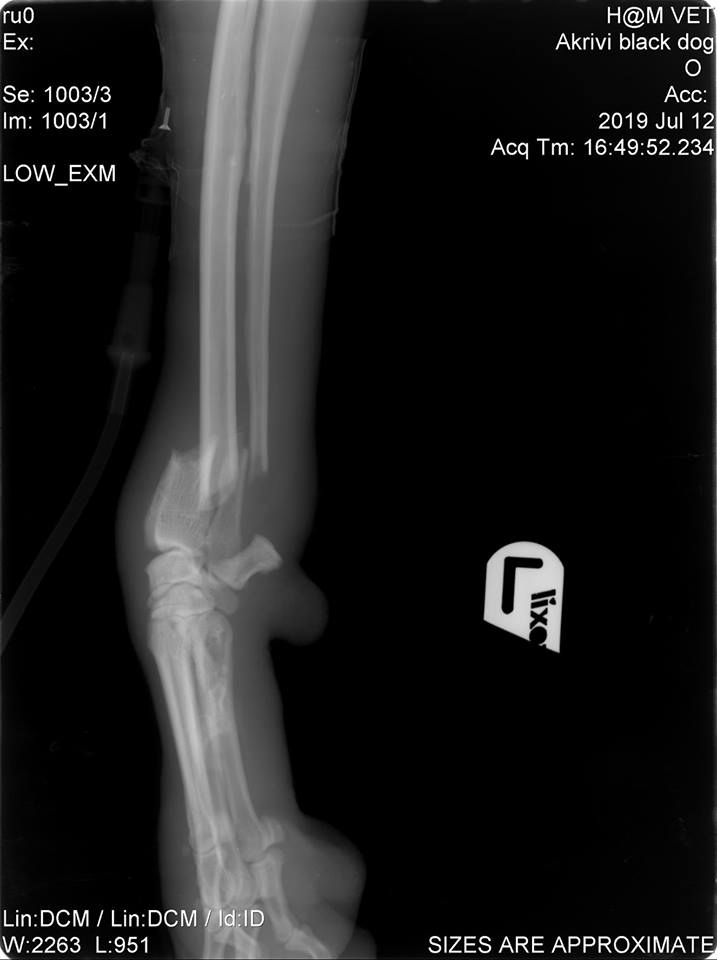

ΕΝΗΜΕΡΩΣΗ 15/7/2019: Η μικρή μας έβγαλε ακτινογραφίες όπου διαπιστώθηκε πως και τα 3 της πόδια χρήζουν άμεσα χειρουργείο! Για το μπροστά αριστερά πόδι έχουμε εγκάρσιο κάταγμα αντιβραχίου. Για το μπροστά δεξί πόδι έχουμε εγκάρσιο κάταγμα βραχιονίου. Για το αριστερό πίσω πόδι έχουμε συντριπτικό κάταγμα κνήμης. Το κεφάλι της είναι σε καλή κατάσταση οπότε δεν χρήζει περαιτέρω εξέτασης.

ΕΝΗΜΕΡΩΣΗ 24/7/2019: Η γλυκιά μας Σάσα πραγματοποίησε και στο τρίτο πόδι το πιο δύσκολο χειρουργείο. Χρησιμοποιήθηκε η μέθοδος Ilizarov (ilizarov external fixator device). Στην προκειμένη φάση θα πρέπει να επισκεπτόμαστε πολύ συχνά τον ορθοπεδικό για αλλαγές και για επίβλεψη του ανοιχτού κατάγματος που είχε το τρίτο πόδι.